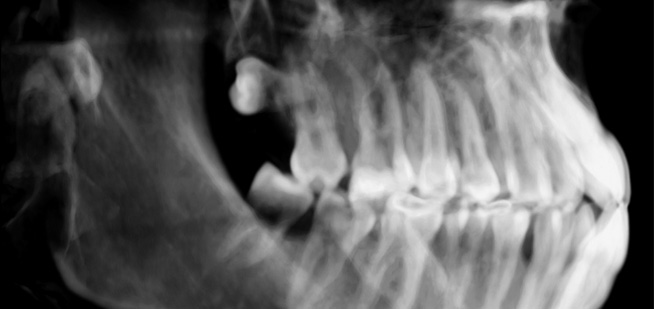

• Die fortschrittliche Technologie ermöglicht Panoramabilder mit präzisem Brennpunkt für den gesamten Kieferbereich.

Endo-Perio

Der Facharzt für Endodontie und Periodontologie benötigt Bilder von absoluter Spitzenqualität und Detailschärfe, um Verfahren wie die Behandlung von Zahnbrüchen, die Heilung von Zahngewebe und die Therapie des Kieferkanals vorzunehmen, da er über genaue Details der behandelten Zone und des Krankheitsbilds verfügen muss, um eine wirkungsvolle Behandlung planen zu können. Nur eine eingehende Untersuchung der betroffenen Areale kann Aufschluss über einen mehr oder weniger invasiven Eingriff geben.